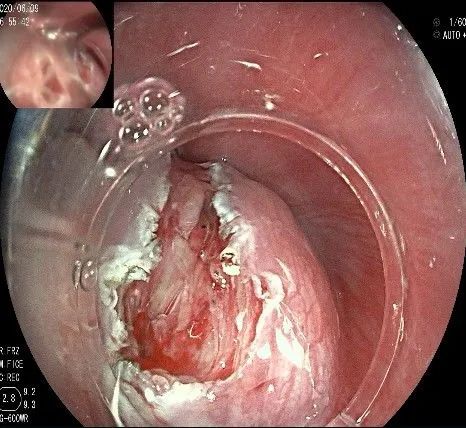

瘤子切除后,在粘膜切开的地方,固有肌层的纵形肌处形成一个开口。

倒镜观察,隆起已经消失。

夹闭创面的时候做胃镜吸引,利于创面闭合。

创面夹闭完成,反复冲洗观察,无出血及穿孔。结束手术,等待病理结果。